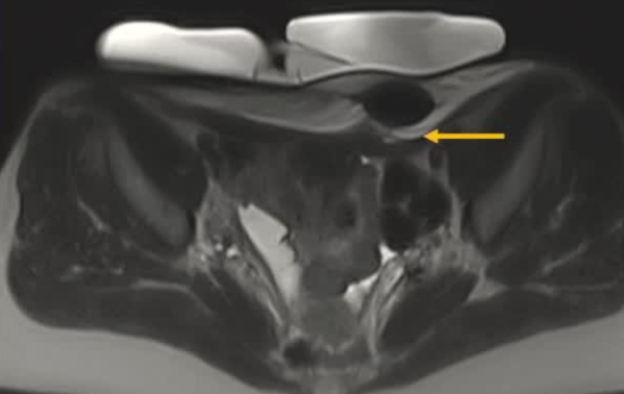

| 腹壁下病变 | MRI引导下 冷冻消融。装有热水的手套在皮肤表面保护皮肤 |

病灶位置:16个疼痛性目标病灶位于脐部(7/16,43.8%)、膈肌(4/16,25.0%)、腹股沟管(3/16,18.8%)和子宫肌肉层(即腺肌症,2/16,12.4%)。

影像引导方式:超声和横断面成像(CT或MRI)结合是最常用的影像引导方式(10/16,62.5%)。

保护措施:几乎所有干预都需要辅助保护措施,其中水分离术(13/16,81.3%)和水分离术与温盐水填充手套的皮肤保护结合(9/16,56.3%)是最常见的保护措施。